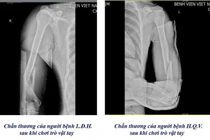

1 tuần 3 trường hợp gãy xương cánh tay từ trò chơi vật tay

Có những trường hợp nhập viện trong tình trạng gãy nham nhở, khó đưa xương về vị trí ban đầu, tổn thương các dây thần kinh quay, trụ và mạch máu lân cận.

Chỉ trong vòng 1 tuần, Khoa Chấn thương Chỉnh hình & Bỏng, Bệnh viện Việt Nam – Thụy Điển Uông Bí đã tiếp nhận 3 trường hợp nhập viện do gãy xương cánh tay, nguyên nhân là từ trò chơi “vật tay”.

Theo bác sĩ Khoa Chấn thương Chỉnh hình & Bỏng cho biết, khi vật tay, lực xoay đột ngột tác động lên xương cánh tay có thể vượt ngưỡng chịu đựng, gây gãy xoắn xương cánh tay, thậm chí di lệch.